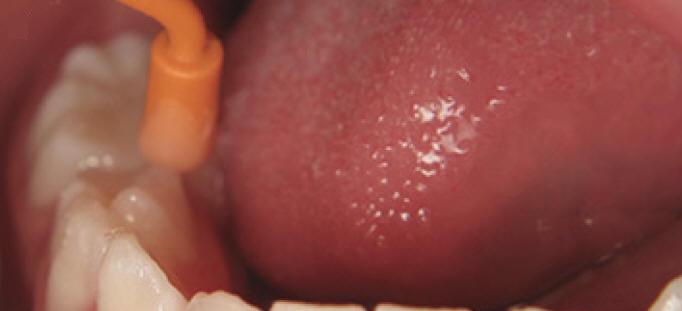

Técnica de aplicación profesional de un agente remineralizante del esmalte y dentina (Mi Paste)

1. Siguiendo la rutina de profilaxis para remover la placa, restos de comida o manchas, pida al paciente que se enjuague la boca.

2. Aplique una generosa capa de MI Paste como parte del terminado final en la superficie de los dientes, utilizando una copa profiláctica ó un cepillo profiláctico. En áreas de difícil acceso use un cepillo inter proximal.

3. Indique al paciente que mantenga el producto MI Paste por lo más que pueda en su boca (1-2 minutos o más) sin  escupir o tragar el producto. Entre más tiempo se mantenga MI Paste en contacto con los dientes, más efectivo será el resultado.

4. Pida al paciente no comer o beber nada en los siguientes 30 minutos después del tratamiento.

Nota: mi paste es usado para remineralizar lesiones iniciales de esmalte, dentina y cemento. También para disminuir la sensibilidad en la unión cemento esmalte (UCE)